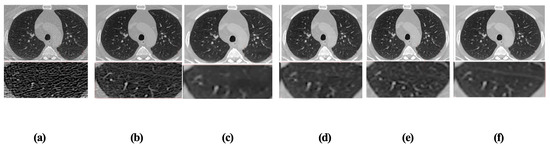

High-Fidelity CT Image Denoising with De-TransGAN: A Transformer-Augmented GAN Framework with Attention Mechanisms

by Usama Jameel and Nicola Belcari

Low-dose computed tomography (LDCT) has become a widely adopted protocol to reduce radiation exposure during clinical imaging. However, dose reduction inevitably amplifies noise and artifacts, compromising image quality and diagnostic confidence. To address this challenge, this study introduces De-TransGAN, a transformer-augmented Generative Adversarial [...] Read more.

Low-dose computed tomography (LDCT) has become a widely adopted protocol to reduce radiation exposure during clinical imaging. However, dose reduction inevitably amplifies noise and artifacts, compromising image quality and diagnostic confidence. To address this challenge, this study introduces De-TransGAN, a transformer-augmented Generative Adversarial Network specifically designed for high-fidelity LDCT image denoising. Unlike conventional CNN-based denoising models, De-TransGAN combines convolutional layers with transformer blocks to jointly capture local texture details and long-range anatomical dependencies. To further guide the network toward diagnostically critical structures, we embed channel–spatial attention modules based on the Convolutional Block Attention Module (CBAM). On the discriminator side, a hybrid design integrating PatchGAN and vision transformer (ViT) components enhances both fine-grained texture discrimination and global structural consistency. Training stability is achieved using the Wasserstein GAN with Gradient Penalty (WGAN-GP), while a composite objective function—L1 loss, SSIM loss, and VGG perceptual loss—ensures pixel-level fidelity, structural similarity, and perceptual realism. De-TransGAN was trained on the TCIA LDCT and Projection Data dataset and validated on two additional benchmarks: the AAPM Mayo Clinic Low Dose CT Grand Challenge dataset and a private clinical chest LDCT dataset comprising 524 scans (used for qualitative assessment only, as no NDCT ground truth is available). Across these datasets, the proposed method consistently outperformed state-of-the-art CNN- and transformer-based denoising models. On the LDCT and Projection dataset head images, it achieved a PSNR of 44.9217 dB, SSIM of 0.9801, and RMSE of 1.001, while qualitative evaluation on the private dataset confirmed strong generalization with clear noise suppression and preservation of fine anatomical details. These findings establish De-TransGAN as a clinically viable approach for LDCT denoising, enabling radiation reduction without compromising diagnostic quality. Full article